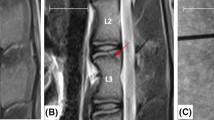

T2-weighted MRI images showed the loss of the NP signal intensity in the disc that underwent nucleotomy compered to controls. The transpedicular tunnel throughout the vertebral body and pedicle was detectable on MRI images (Fig. 5).